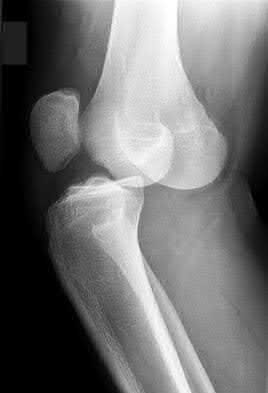

1. # A 32-year-old male sustains the injury shown in Figure A and undergoes treatment as shown in Figure B. Following placement of this implant, what is the best technique to confirm it is not too proud proximally?

1. Lateral radiograph of the knee

The safe zone for tibial nail placement as seen on radiographs is just medial to the lateral tibial spine on the anteroposterior radiograph and immediately adjacent and anterior to the articular surface as visualized on the lateral radiograph.

Tornetta et al specifically located the safe zone for nail entry in a study using fresh frozen cadaver knees. The authors found that the safe zone for nail placement is located 9.1+/-5 millimeters lateral to the midline of the plateau and three millimeters lateral to the center of the tibial tubercle. The width of the safe zone averaged 22.9 millimeters and was as narrow as 12.6 millimeters.

The starting point of the of the nail can be best viewed on the lateral knee radiograph, an example of which is shown in Illustration A. Illustration B shows the "sweet spot" for nail insertion as defined by Tornetta.